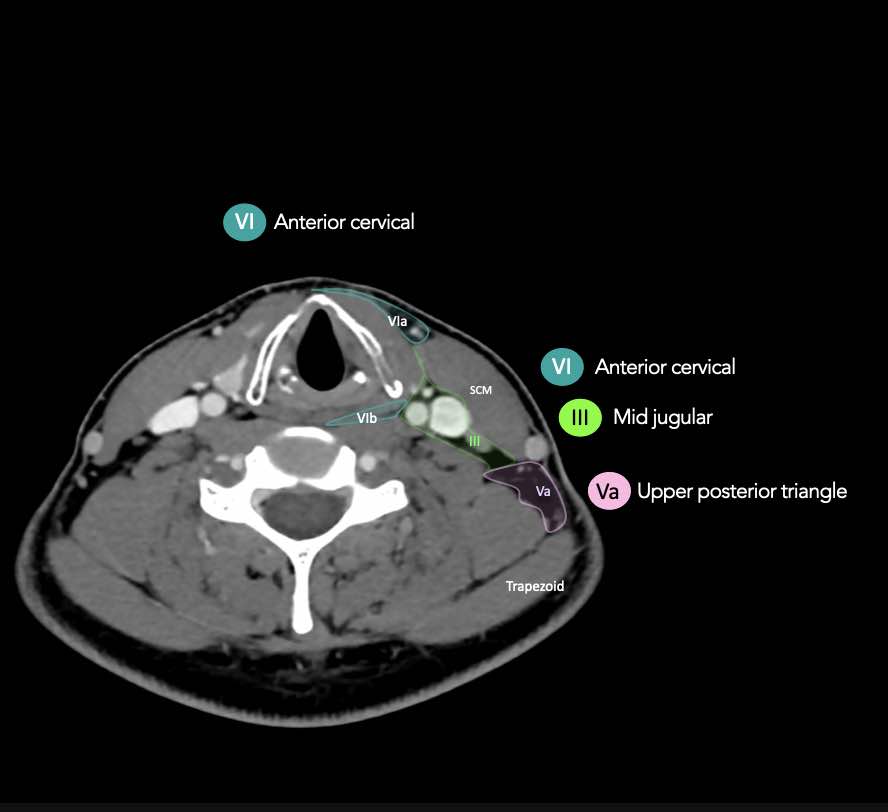

CT Scan Mặt Cắt Ngang (Axial CT)

Các lát cắt CT mặt phẳng ngang tương ứng với hình minh họa tổng quan.

Các lát cắt CT mặt phẳng ngang với hình ảnh chi tiết hơn.

Nhấp vào hình ảnh để phóng to.

V – Tam giác cổ sau và hố thượng đòn

Tầng V chứa các hạch của nhóm tam giác cổ sau nằm ở phía sau cơ ức đòn chũm, xung quanh phần dưới của thần kinh phụ gai sống và các mạch máu cổ ngang.

Các hạch bạch huyết ở tầng V thường liên quan nhất đến các ung thư nguyên phát của vòm hầu, hầu miệng, các cấu trúc da vùng da đầu phía sau và tuyến giáp.

VI – Cổ trước

Tầng này chứa các hạch tĩnh mạch cảnh trước nông (tầng VIa) và các hạch sâu hơn bao gồm hạch trước thanh quản, trước khí quản, cạnh khí quản và hạch thần kinh thanh quản quặt ngược (tầng VIb).